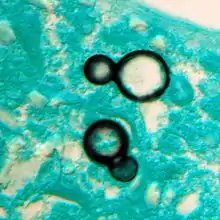

Zymonema dermatitidis, formerly called Blastomyces dermatitidis

- A taxonomic genus within the subphylum Pezizomycotina – certain ascomycetous fungi.

- (genus): Zymonema dermatitidis - type species